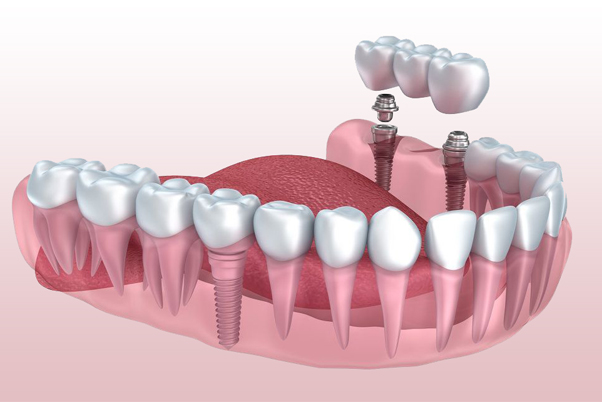

由美国John Chao牙外科博士发明并获得专利的针孔微创技术手术/针孔牙龈恢复术(Pinhole® Surgical Technique/ Pinhole Gum Rejuvenation®)是一种无手术刀,无缝合的治疗牙龈退缩的尖端新科技。

由美国John Chao牙外科博士发明并获得专利的针孔微创技术手术/针孔牙龈恢复术(Pinhole® Surgical Technique/ Pinhole Gum Rejuvenation®)是一种无手术刀,无缝合的治疗牙龈退缩的尖端新科技。

这种方法是通过在牙龈组织上打一个小孔来执行此过程。使用专门设计的工具,将牙龈组织松开并引导至牙齿的后退部分。由于没有切割或缝合,因此患者可以预期的术后症状(疼痛,肿胀和出血)最少。大多数患者对美容效果的即时改善也感到惊喜。